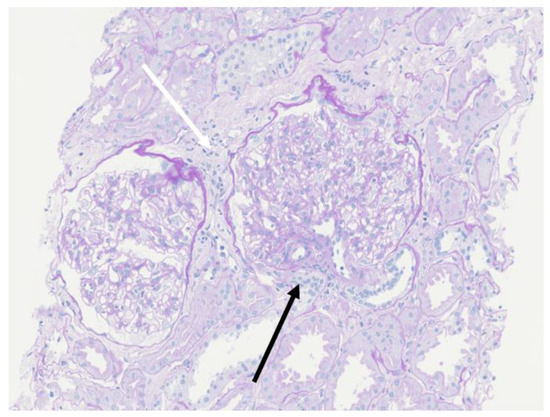

A percutaneous renal biopsy demonstrated that 1 out of 8 glomeruli had segmental sclerosis with adhesion to the Bowman’s capsule (black arrow), and white arrow indicated partial focal interstitial fibrosis (Figure 1). The mean diameter of the glomeruli was 348.23 μm, which was much larger than that of normal glomeruli (168 ± 12 μm) [7]. Immunofluorescence analyses (IgG, IgA, IgM, C3, C1q and C4) were all negative. These biopsy findings supported a diagnosis of FSGS.

Figure 1. The mean diameter of the glomeruli of this patient (348.23 μm) was much larger than that of normal glomeruli (168 ± 12 μm). Periodic Acid Schiff staining (magnification: 200×). White arrow: partial focal interstitial fibrosis. Black arrow: segmental sclerosis with adhesion to the Bowman’s capsule.